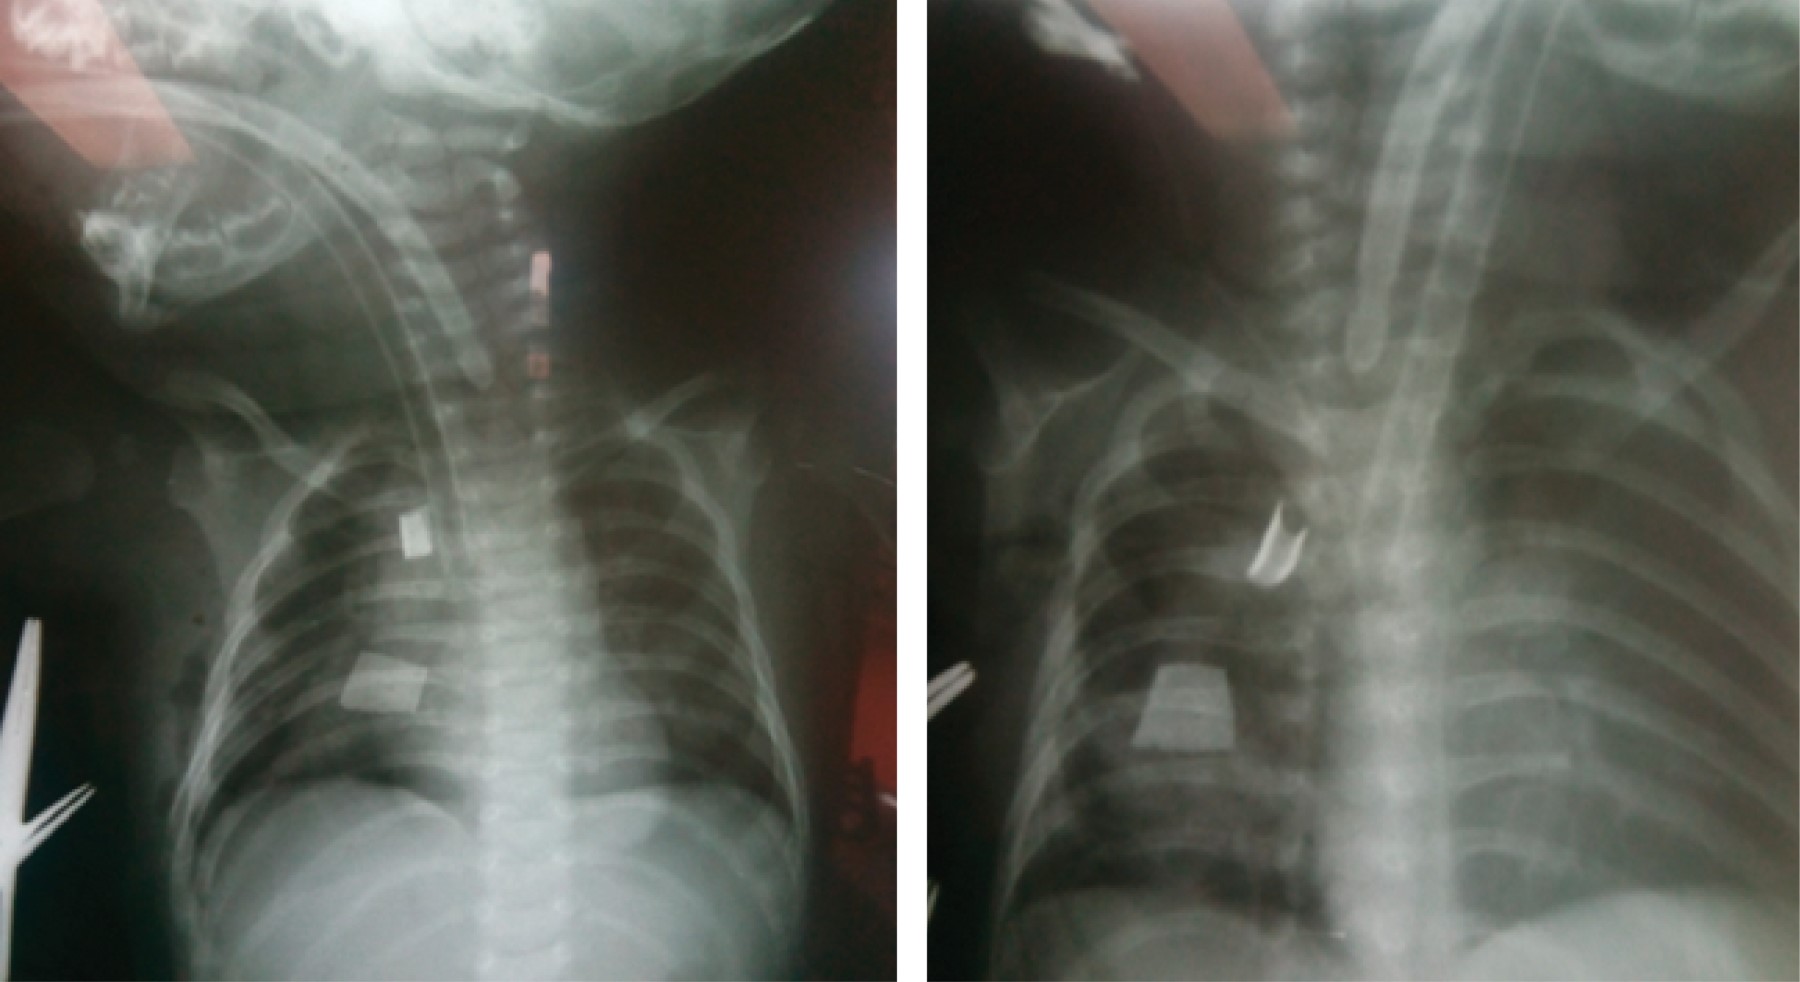

Con este avance se realiza toracotomía posterolateral derecha, con abordaje extrapleural, disecando ambos cabos esofágicos (incluyendo disección hiatal de cabo inferior) y colocando jaretas de seda, las cuales se exteriorizan para una elongación esofágica tipo Foker (Figuras 3 y 4), con tracciones seriadas cada 24 horas y controles radiográficos diarios en los que se permite visualizar la aproximación de los marcadores radiopacos colocados en ambos cabos (Figura 5).

Tras 20 días de tracción esofágica, presenta ruptura incidental de las jaretas de seda para elongación extratorácica, en este momento la brecha se midió de dos cuerpos vertebrales y medio, con una ganancia en el cierre de la brecha esofágica en promedio de 4 mm/día. Pasa a quirófano para segunda toracotomía, aún se encuentra mucha dificultad para la aproximación esofágica, por lo que se hace uso de técnicas combinadas para lograr la anastomosis esofágica con la menor tensión posible, éstas fueron: la técnica de Livaditis (miotomía esofágica), Gough (colgajo esofágico) y Bagolan (tensión transquirúrgica de cabos) (Figura 6). Se logró la continuidad esofagogástrica a los 76 días de vida.

Figura 3

Figura 4